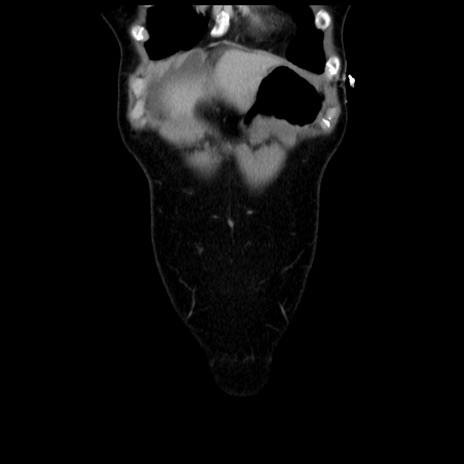

症例10(冠状断像)

【症例】 50歳代女性

【主訴】 腹痛

【現病歴】前日生レバーを食べた。今朝に排便あり。 昼前に突然発症の腹痛を生じ、当院救急外来を受診した。

【既往歴】 子宮筋腫にてで子宮全摘後

【身体所見】 意識清明、腹部:平坦、軟、下腹部やや左を中心に圧痛・反跳痛あり、筋性防御あり

【データ】WBC 7800、CRP 0.07